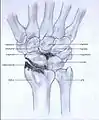

Stages

Post-traumatic osteoarthritis can be classified into four stages.[1][6] These stages are similar between SLAC and SNAC wrists. Each stage has a different treatment.

- Stage III: the osteoarthritis is localized in the entire radioscaphoid joint with involvement of the capitolunate joint.

- Stage IV: the osteoarthritis is located in the entire radiocarpal joint and in the intercarpal joints. It also may involve the distal radio-ulnar joint (DRUJ).

Stage III

Stage IV